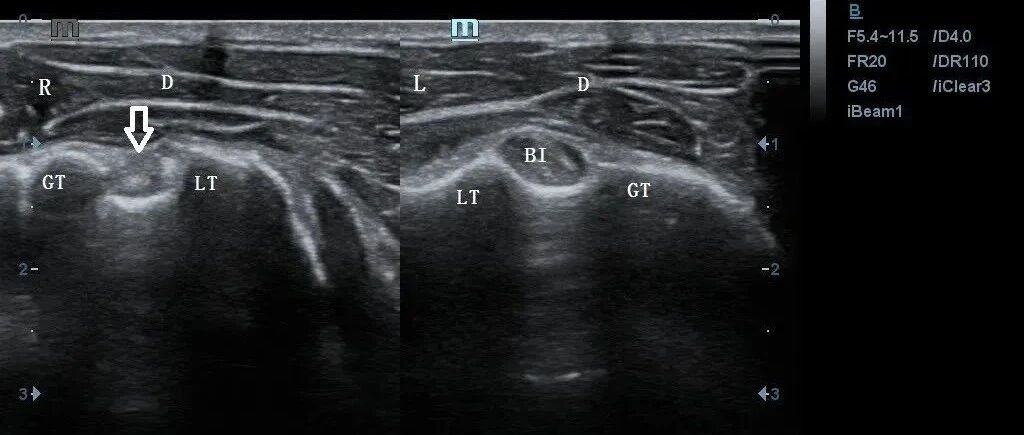

「大力水手征」你见过吗? 丁香园超声时间 · 公众号 · 医学 · 1 年前 · |